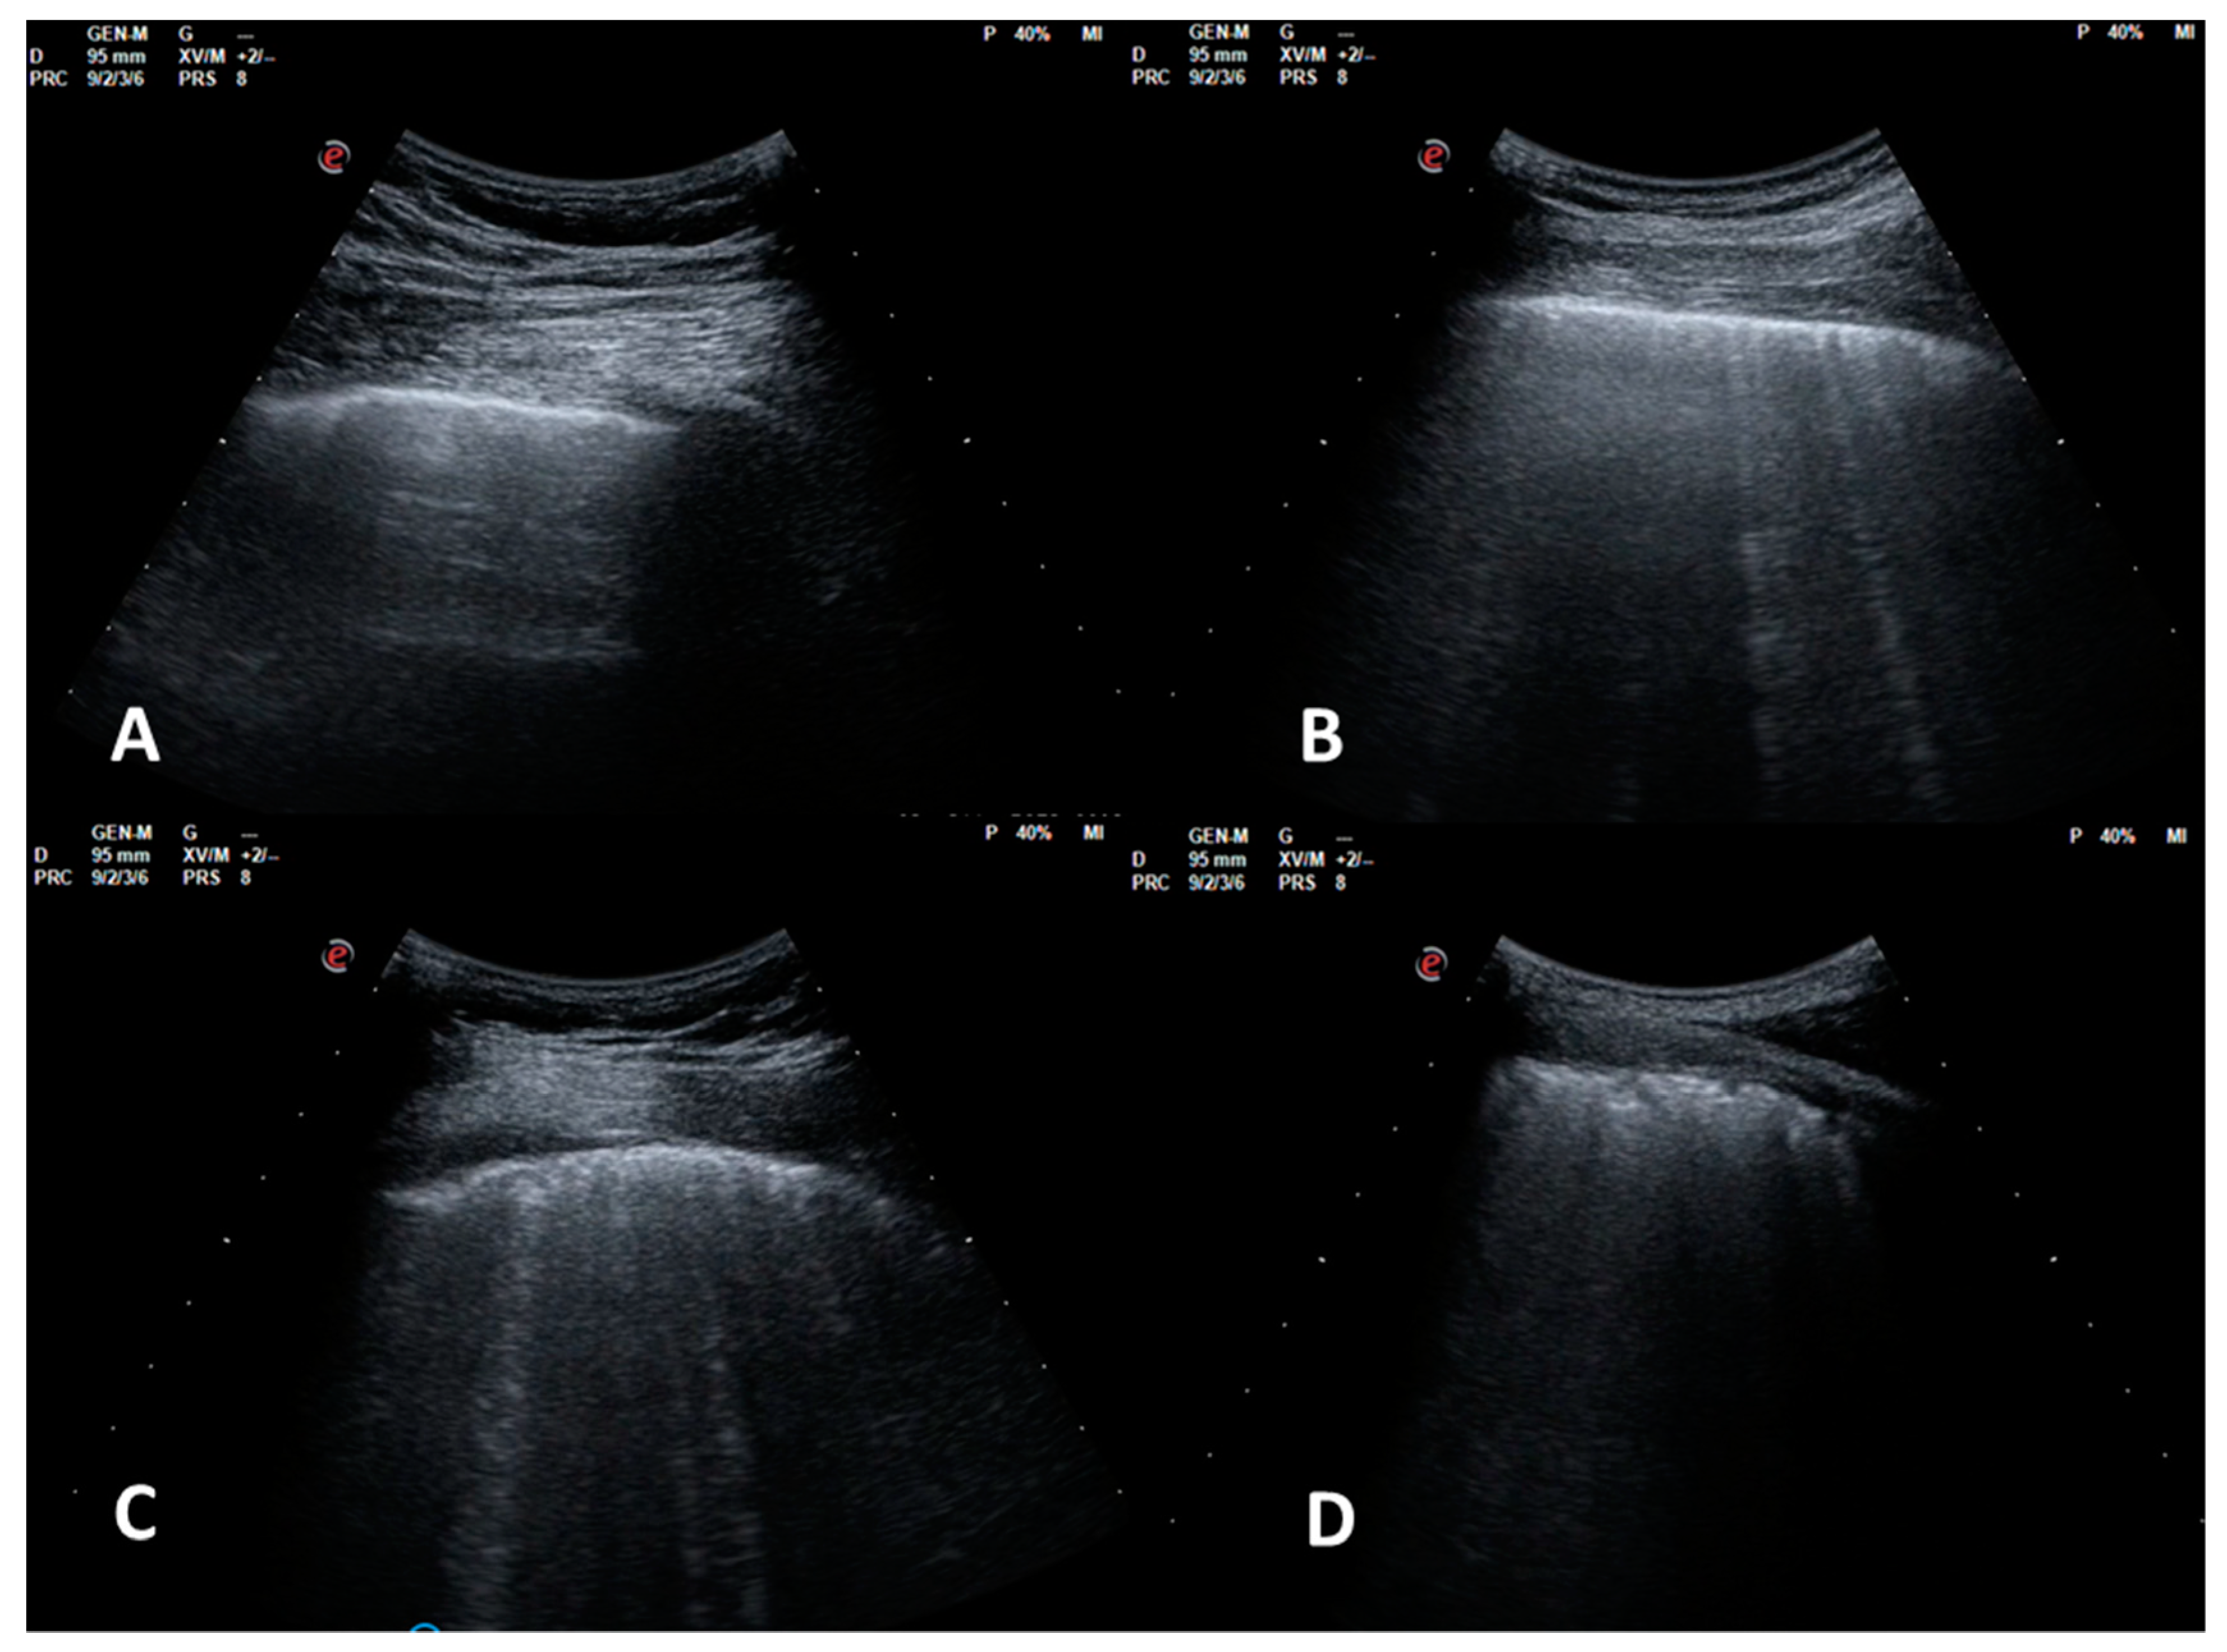

2.1. Ultrasonography